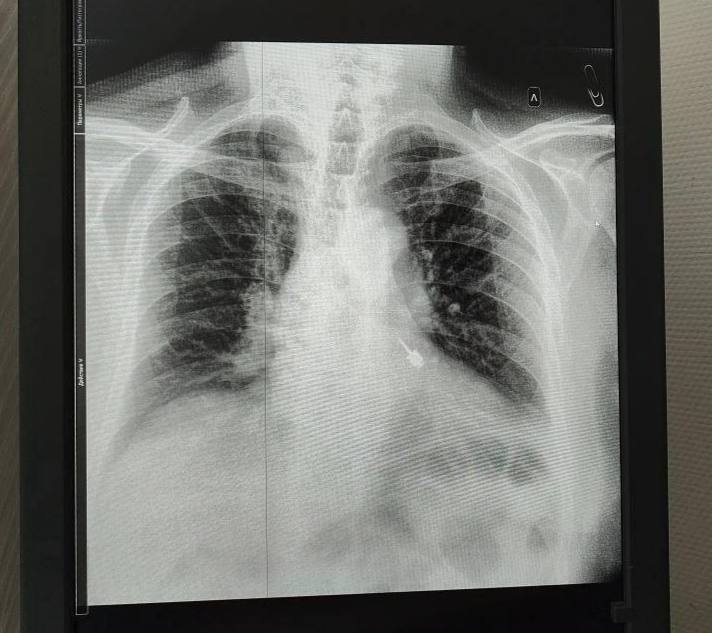

Рентген показал, что острый инструмент застрял в левом бронхе. Любое промедление грозило кровотечением и осложнениями, вплоть до смертельного исхода.